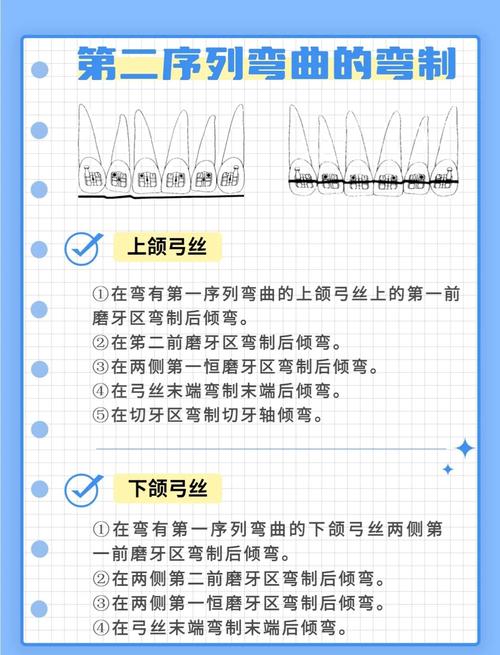

(三)转矩与轴倾度控制

转矩是方丝沿长轴旋转产生的力,用于控制牙齿的唇舌向倾斜(如上颌前牙根舌倾、下颌前牙根唇倾),弯制时需用转矩钳,将方丝嵌入钳子垂直槽沟中,旋转钳子至所需角度(如上颌前牙转矩+13°,下颌前牙转矩-7°),旋转范围不超过45°,避免弓丝变形,轴倾度通过在托槽槽沟内调整弓丝角度实现,如磨牙近中倾斜5°,防止近中移动时支抗丧失。